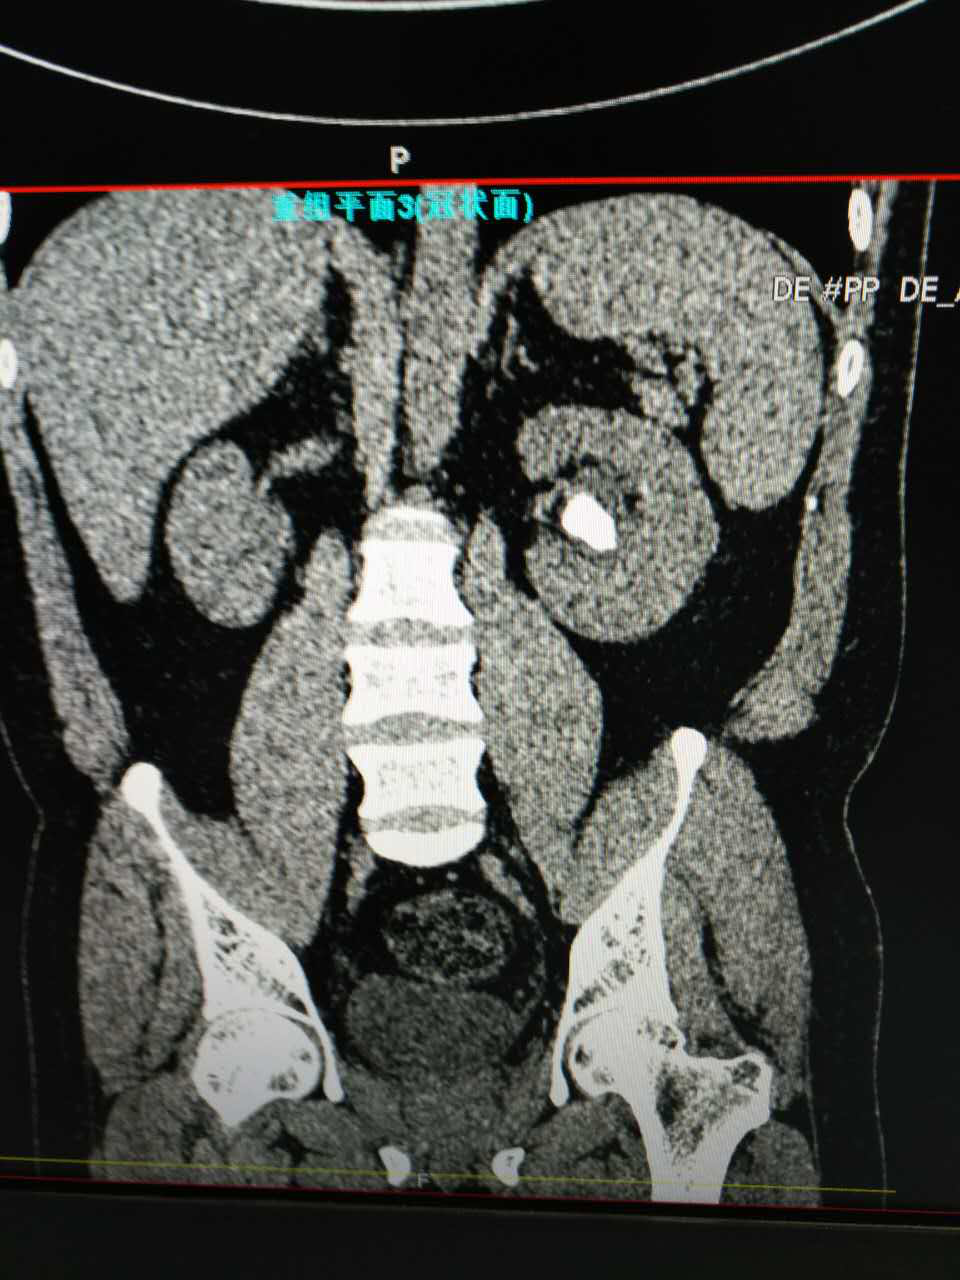

近日,我院泌尿外科成功开展孙氏末端输尿管软镜碎石术,顺利为一例复杂性肾结石患者碎石,手术过程顺利,目前患者已康复出院。

患者,青年男性,因肾结石先后就诊于多家医院,无明显效果后,经多方打听来我院泌尿外科李朝明主任处就诊。李主任在详细了解了患者病情后,最终决定行孙氏末端输尿管软镜碎石术,手术过程顺利,术后患者恢复良好,碎石后排石量达肾结石95%以上,碎石效果明显。

“软镜取石”是继药物排石、体外冲击波碎石、钬激光碎石、经皮肾镜碎石、EMS碎石清石系统之后所开展的又一项新技术。该手术的顺利开展为泌尿系统疾病的诊治提供了新的手段,进一步提升了本科室的微创技术水平,标志着我院泌尿外科在内镜治疗结石方面实现了新的突破,这一技术必将得到更为广泛的应用,为更多患者带来福音。

我院于2015年购置孙氏末端输尿管软镜,泌尿外科李朝明主任先后赴广州医学院附属第一医院、第二军医大学长海医院泌尿外科腔镜中心进修学习,于2015年8月开展输尿管软镜手术,目前已完成近50例,碎石成功率100%,无一例中转开放手术。